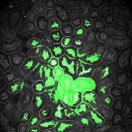

The first row in Figure 3 displays an original microscopy image (), its inhomogeneity corrected version (), and manually delineated groundtruth (), respectively. For brevity we have omitted the superscript in the notation. The second row shows segmentation results of various 3D methods such as 3D region-based active contours [10] (3Dac), 3D active contours with inhomogeneity correction [11] (3DacIC), and 3D Squassh presented in [12] (3Dsquassh). Similarly, the third row portrays various segmentation methods particularly designed for tubular structure segmentation such as ellipse fitting method presented in [15] (Ellipse Fitting), the Jelly filling method in [20] (Jelly Filling), and tubule segmentation using steerable filter [21] (Steerable Filter). Finally, the last row shows segmentation results of our proposed CNN architecture without inhomogeneity correction [27] (2DCNN) and with inhomogeneity correction (2DCNNIC).

For visual comparison we highlighted groundtruth regions in red, segmented tubule regions in green, and background in black. As observed in Figure 3, our proposed method appeared to perform better than the other six methods shown in the second and third rows by distinguishing tubules and was similar performance to 2DCNN. Note that since some methods such as Ellipse Fitting, Jelly Filling, and Steerable Filter only segmented boundaries of tubule structures, tubule interiors were filled in order to perform a fair comparison using connected components with a -neighborhood systems. Also, based on the assumption that tubule regions should contain lumen, if a filled region contained lumen pixel, the region was identified as a tubule region. However, if a filled region did not contain any lumen pixels, the region was considered as a background region.

The segmentation results shown in the second row generally missed many tubule regions. More specifically, 3Dac and 3Dsquassh could not capture the tubular structures but captured some in the center regions due to the intensity inhomogeneity of microscopy images. 3DacIC failed to segment tubular structures but captured multiple lumens inside tubules as well as some tubule boundaries. In contrast, the segmentation results displayed in the third row showed falsely detected tubules. The main reason is that these tubule segmentation methods focused only on detecting boundaries of tubular structures. In particular, due to weak/blurry edges of fluorescence microscopy images, many boundaries were not continuous causing the filling operation to overflow from one tubule to another or to the background regions. The segmentation results using the CNN generally successfully segmented and identified each tubule region.

Figure 4 provides an alternative way to show the segmentation results. In particular, yellow regions correspond to true positives which are pixel locations that are identified as tubules in both the groundtruth and segmentation results. Green regions correspond to false positives which are pixel locations that are identified as background in groundtruth but tubules in segmentation results. Similarly, red pixels correspond to false negatives, namely pixel locations identified as tubules in the groundtruth but background in segmentation results, and black pixel regions correspond to true negative that are identified as background in both groundtruth and segmentation results. The green regions indicate Type-I error (false alarm) regions and the red regions represent Type-II error (miss) regions. As observed from Figure 4, the segmentation results in the first row contained large red regions which mean large regions of tubules were missed. Conversely, the segmentation results shown in the second row contained many green regions indicating many background regions were falsely segmented as tubule regions. In contrast, the segmentation results in the third row had reasonably small green regions and red regions which indicate that the deep learning based segmentation results had higher pixel accuracy with relatively low Type-I and Type-II errors.